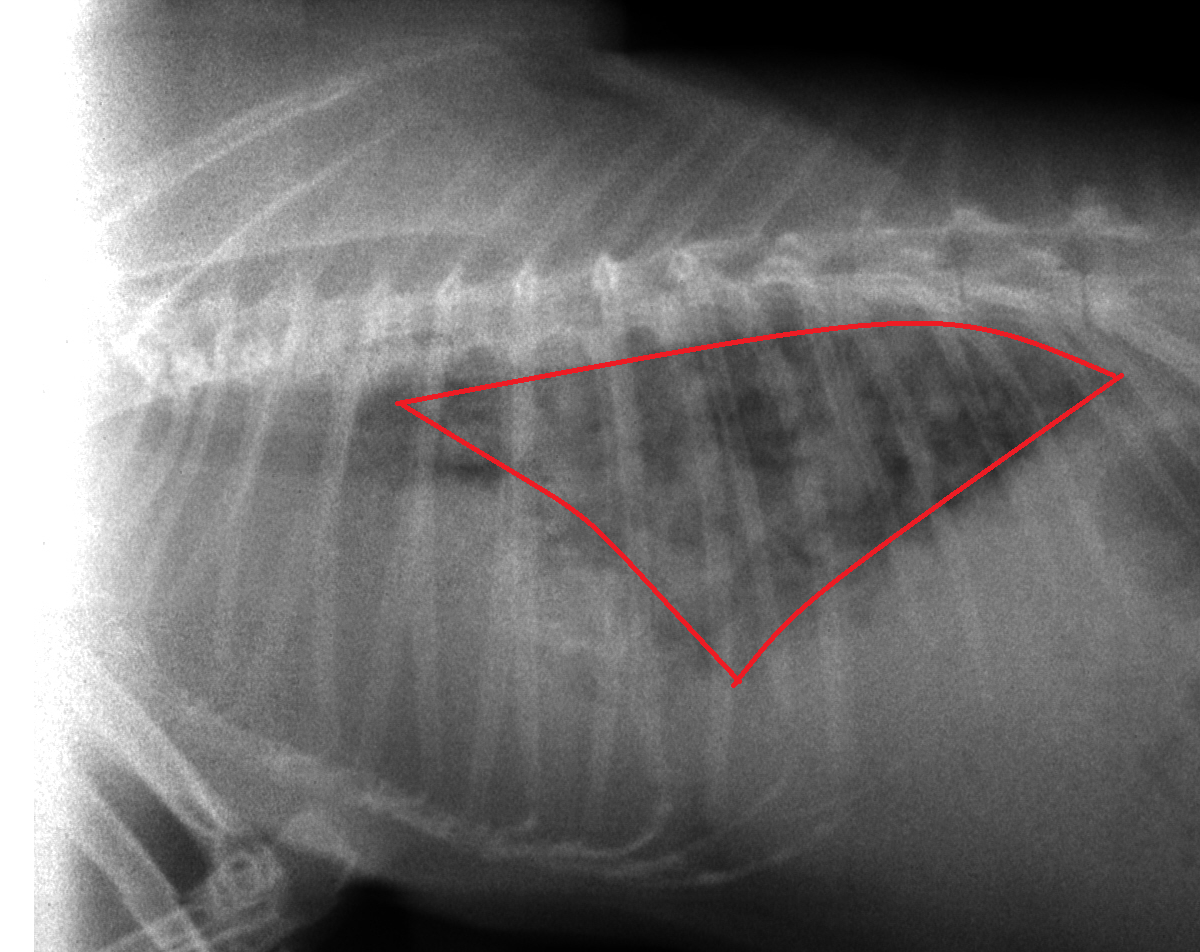

呼吸の悪いうさぎさん 浜村動物病院 うさぎさんのページ